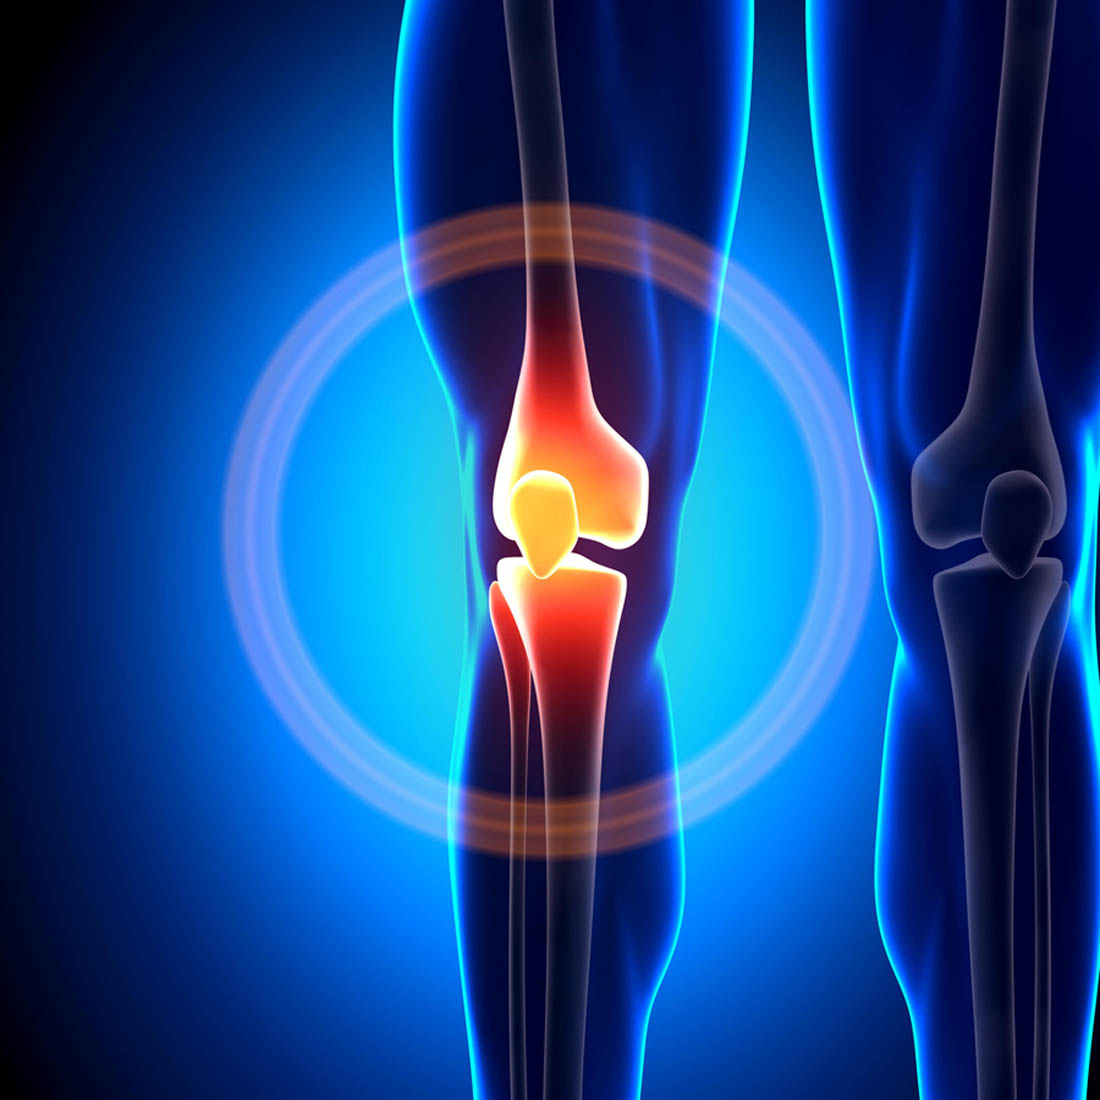

Your Expert in Comprehensive Joint Care.

Proven Expertise in Restoring Mobility, a Track Record of Excellence, and Advanced, Compassionate Care for Optimal Orthopedic Health